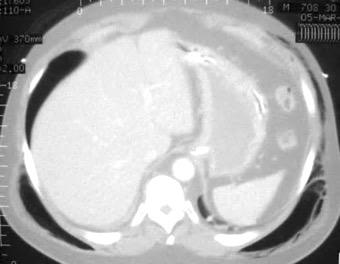

Marzo 2014: Perforación longitudinal distal secundaria a episodio de vómito (síndrome de Boerhaave). Derrame pleural izdo. que evoluciona a empiema.

Wang C-T et al. Tension hydropneumothorax in a Boerhaave syndrome patient: A case report . World J Emerg Med, 2021. Katabathina V et al. Nonvascular, nontraumatic mediastinal emergencies in adults:a comprehensive review of imaging findings. Radiographics. 2011.